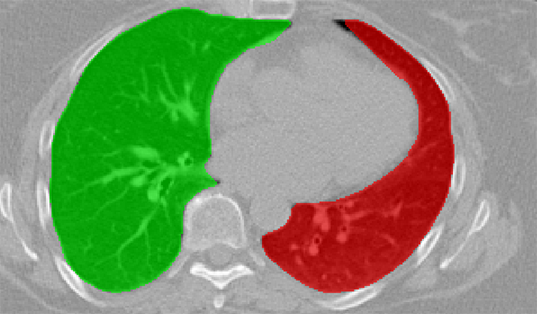

We applied our method on PET-CT scans of three different subjects to segment their liver, left kidney, right kidney and the background. Although we applied our method and Potts model on the 3D volumes we only show the results on a few representative slices from each volume in Fig.11. Also, the results of different methods for each subject were computed using the same smoothness. We can see from the last two rows which compare our method to Potts, using Hedgehogs constraints enabled us to avoid geometrically incorrect segmentations, e.g. one liver inside the other (last-row middle), or parts of left kidney is between the right kidney and liver (last-row right). Furthermore, for test subjects 1 and 2 the kidneys and background were poorly segmented by Potts model, e.g. most of the kidneys were segmented as background for test subject 1. Potts poor performance is due to the large overlap between the kidneys and background color models. This overlap resulted in an in-discriminative data term for Potts to properly separate them. This issue becomes worse in iterative frameworks where color models are re-estimated based on current segmentation. To be specific, if at any iteration Potts model resulted in a bad segmentation then re-estimating the color models will bias them towards the bad segmentation and subsequent iterations worsen the results. Comparing our results for subjects 1 and 2 to Potts model shows that our method is less prone to the aforementioned issue as we forbid undesirable segmentations, i.e. those that do not respect shape constraints.

For quantitative comparison, Table 1 lists for each organ of a subject the Score, Precession and Recall measures of our method and Potts model where For the kidneys, our method clearly out performed Potts model, e.g. note Potts model poor precision/recall for subjects 1 and 2. For the liver, both methods performed comparably.